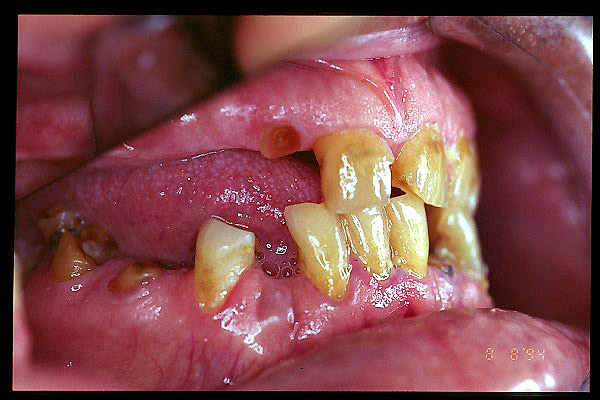

CM Extrusión de incisivos inferiores por falta de contactos oclusales